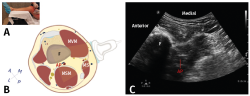

Bloqueo IPACK

Consiste en administrar anestésico local guiado por ecografía entre la cápsula posterior de la rodilla y la arteria poplítea, para proveer analgesia en la cara posterior de la rodilla, bloqueando las ramas articulares de los nervios tibial, peroneo común y obturador, evitando el bloqueo motor y, por lo tanto, permitiendo una deambulación y una rehabilitación precoces (Figura 5)(15). Es una de las técnicas más nuevas, con gran cantidad de artículos recientes publicados, sobre todo para artroplastia de rodilla.

Es útil como opción al bloqueo del nervio ciático para la cirugía de rodilla y generalmente complementado con un bloqueo de la inervación de la cara anterior de la rodilla (femoral vs. canal de los aductores). Se utiliza un volumen medio de anestésico local de 15-20 mL.

Figura 5. Bloqueo IPACK. A: posición del paciente y de la sonda del ecógrafo; B: diagrama de la posición de la sonda y área explorada; C: visión ecográfica; AP: arteria poplítea; F: fémur; MS: músculo sartorio; MSM: músculo semimembranoso; MVM: músculo vasto medial(15).